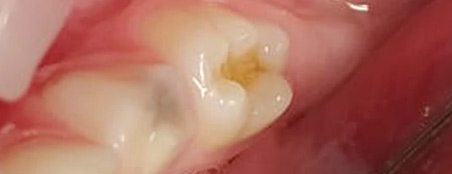

Эстетические реставрации. Дошколятам нравятся цветные пломбы, а детям постарше врач поставит пломбу, точь-в-точь совпадающую по цвету, форме и рельефу с натуральным зубом.

Зачаток постоянного зуба расположен прямо под корнями молочного. Если в молочном зубе инфекция, она часто переходит на постоянный зуб. В результате тот прорезывается уже нездоровым или не вырастает совсем.

В зубах с нелечеными кариозными полостями обитают стафилококки и стрептококки. Постоянный очаг инфекции снижает иммунитет ребенка, повышает риск ОРЗ и болезней внутренних органов.